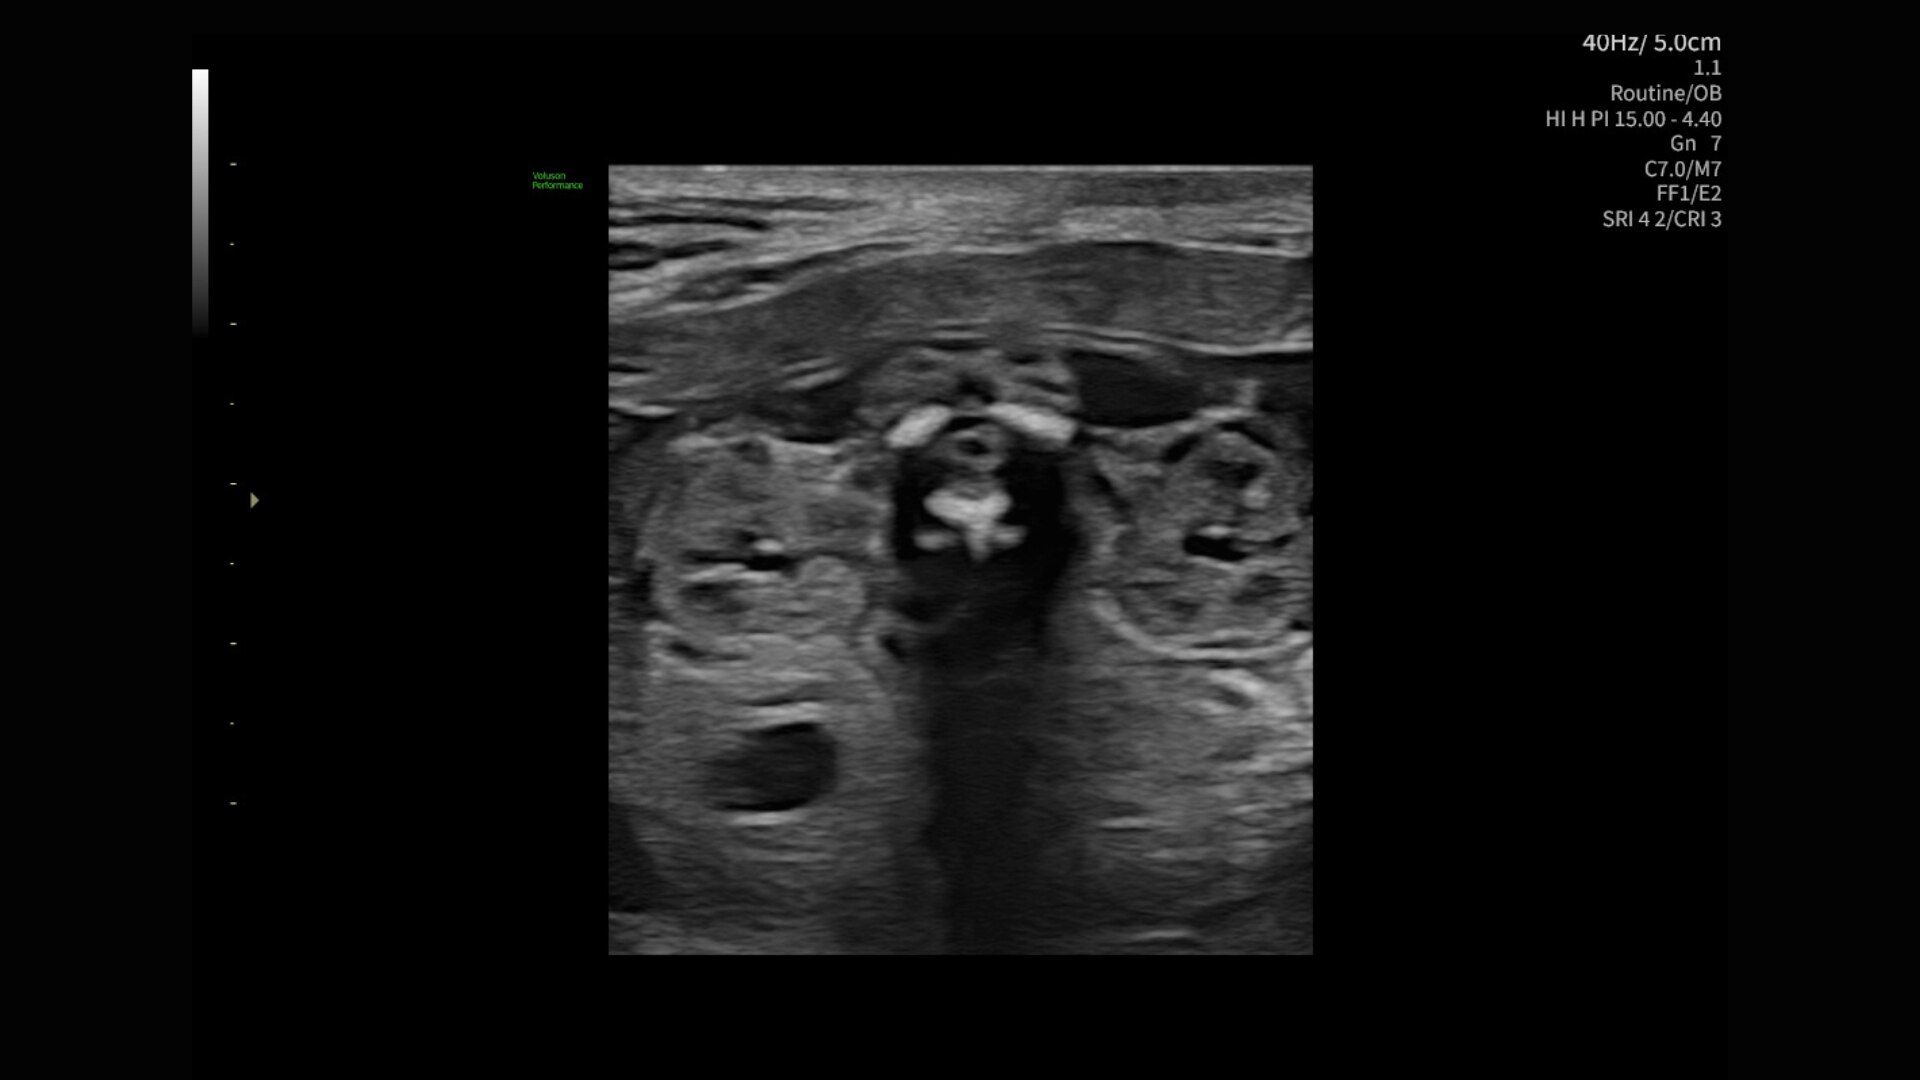

Image quality

Excellent images that are easy to acquire

Image quality is everything in ultrasound

The Voluson Performance 18 delivers high-resolution, detailed imaging with one-touch optimization for effortless scanning—helping you deliver quick, confident answers across a wide range of patient.